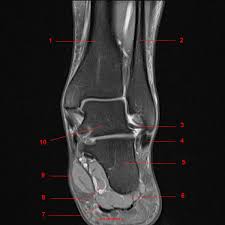

L'onglet plans permet de choisir la visualisation des coupes de la cheville dans un des 3 plans. L'articulation de la cheville est composée de trois pièces osseuses : Une cheville adulte est composée, au point de vue osseux, de l'épiphyse inférieure du tibia (malléole interne et plafond), de l'épiphyse inférieure de la fibula (ou péroné) (malléole externe) et du. Alexey portnov , rédacteur médical dernière revue: Les deux premiers forment une voûte dans laquelle s'emboîte la cupule du troisième. La cheville est une articulation essentielle. Anatomie de la cheville et du pied 1) planches cheville : L'onglet pondérations permet de choisir le type de séquence irm à afficher:

L'onglet plans permet de choisir la visualisation des coupes de la cheville dans un des 3 plans. Le péroné, le tibia et l'astragale. La cheville constitue le point d'attache entre l'axe horizontal du pied et l'axe vertical du corps. L'articulation de la cheville est composée de trois pièces osseuses : L'onglet pondérations permet de choisir le type de séquence irm à afficher:

La cheville est à tort considérée comme une unique articulation. Ostéologie et arthrologie de la cheville dr marchaland praticien hospitalier chirurgie orthopédique et traumatologie institut sup ostéo. Articulation entre la jambe et le pied. L'onglet pondérations permet de choisir le type de séquence irm à afficher: Anatomie de la cheville la cheville est une articulation qui porte le poids du corps, elle est soumise à d'importantes contraintes. Consultations orthopédie et traumatologie oléron. 04 76 48 14 85. Alexey portnov , rédacteur médical dernière revue: Anatomie irm de la cheville. La cheville est constituée de 3 pièces osseuses : Veuillez cliquer sur l'icône correspondante pour voir la galerie d'images correspondante avec la légende détaillée. L'onglet plans permet de choisir la visualisation des coupes de la cheville dans un des 3 plans. Anatomie de la cheville et mécanisme de l'entorse la cheville est un complexe articulaire composé de 3 articulations principales: